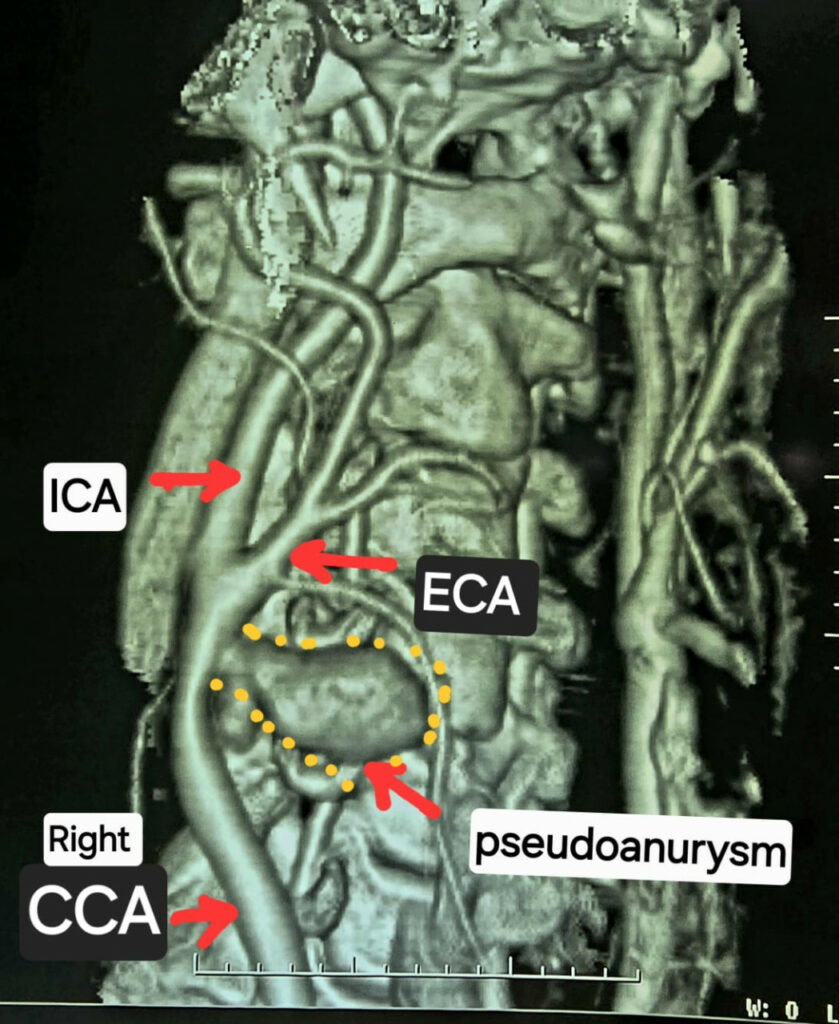

Mekahara Hospital Surgery News: गर्दन के नसों की सीटी एंजियोग्राफी जांच में यह चौंकाने वाला तथ्य सामने आया कि मरीज की दायीं कैरोटिड आर्टरी फट चुकी है और उसके चारों ओर गुब्बारानुमा संरचना बन गई है, जिसे कैरोटिड आर्टरी स्यूडोएन्युरिज्म (Carotid Artery Pseudoaneurysm) कहा जाता है। स्थिति की गंभीरता को देखते हुए मरीज को तत्काल हार्ट, चेस्ट एवं वैस्कुलर सर्जरी विभाग में डॉ कृष्ण कांत साहू के पास भेजा गया।

बोवाइन पेरिकार्डियम पैच से की गई धमनी की मरम्मत

लगभग कई घंटे चले इस चुनौतीपूर्ण ऑपरेशन में बोवाइन पेरिकार्डियम पैच की सहायता से फटी हुई कैरोटिड आर्टरी को अत्यंत सावधानीपूर्वक रिपेयर किया गया। सर्जरी पूरी तरह सफल रही और राहत की बात यह रही कि मरीज को किसी भी प्रकार का लकवा नहीं हुआ। वर्तमान में मरीज पूरी तरह स्वस्थ है।